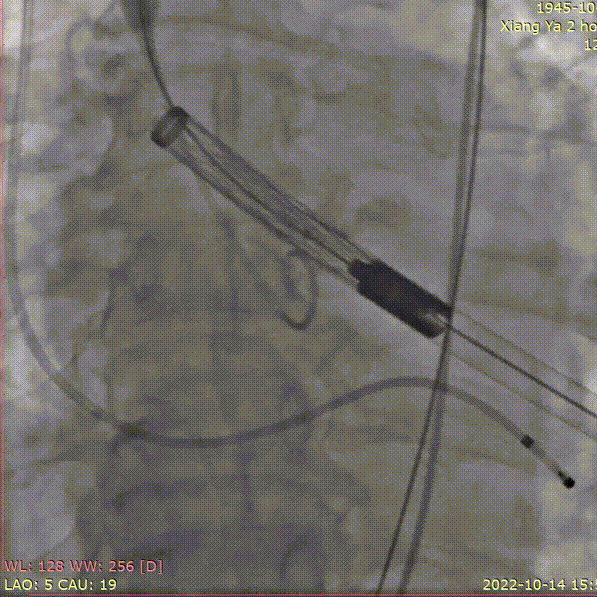

手术关键步骤

A.主动脉根部造影

B. 20mm球囊预扩张

C. 应用交界贴合技术调整人工瓣膜,输送系统内支架最下缘平齐标准位释放瓣膜

D. 瓣膜释放后造影

E.25mm球囊后扩张

F. 最终造影